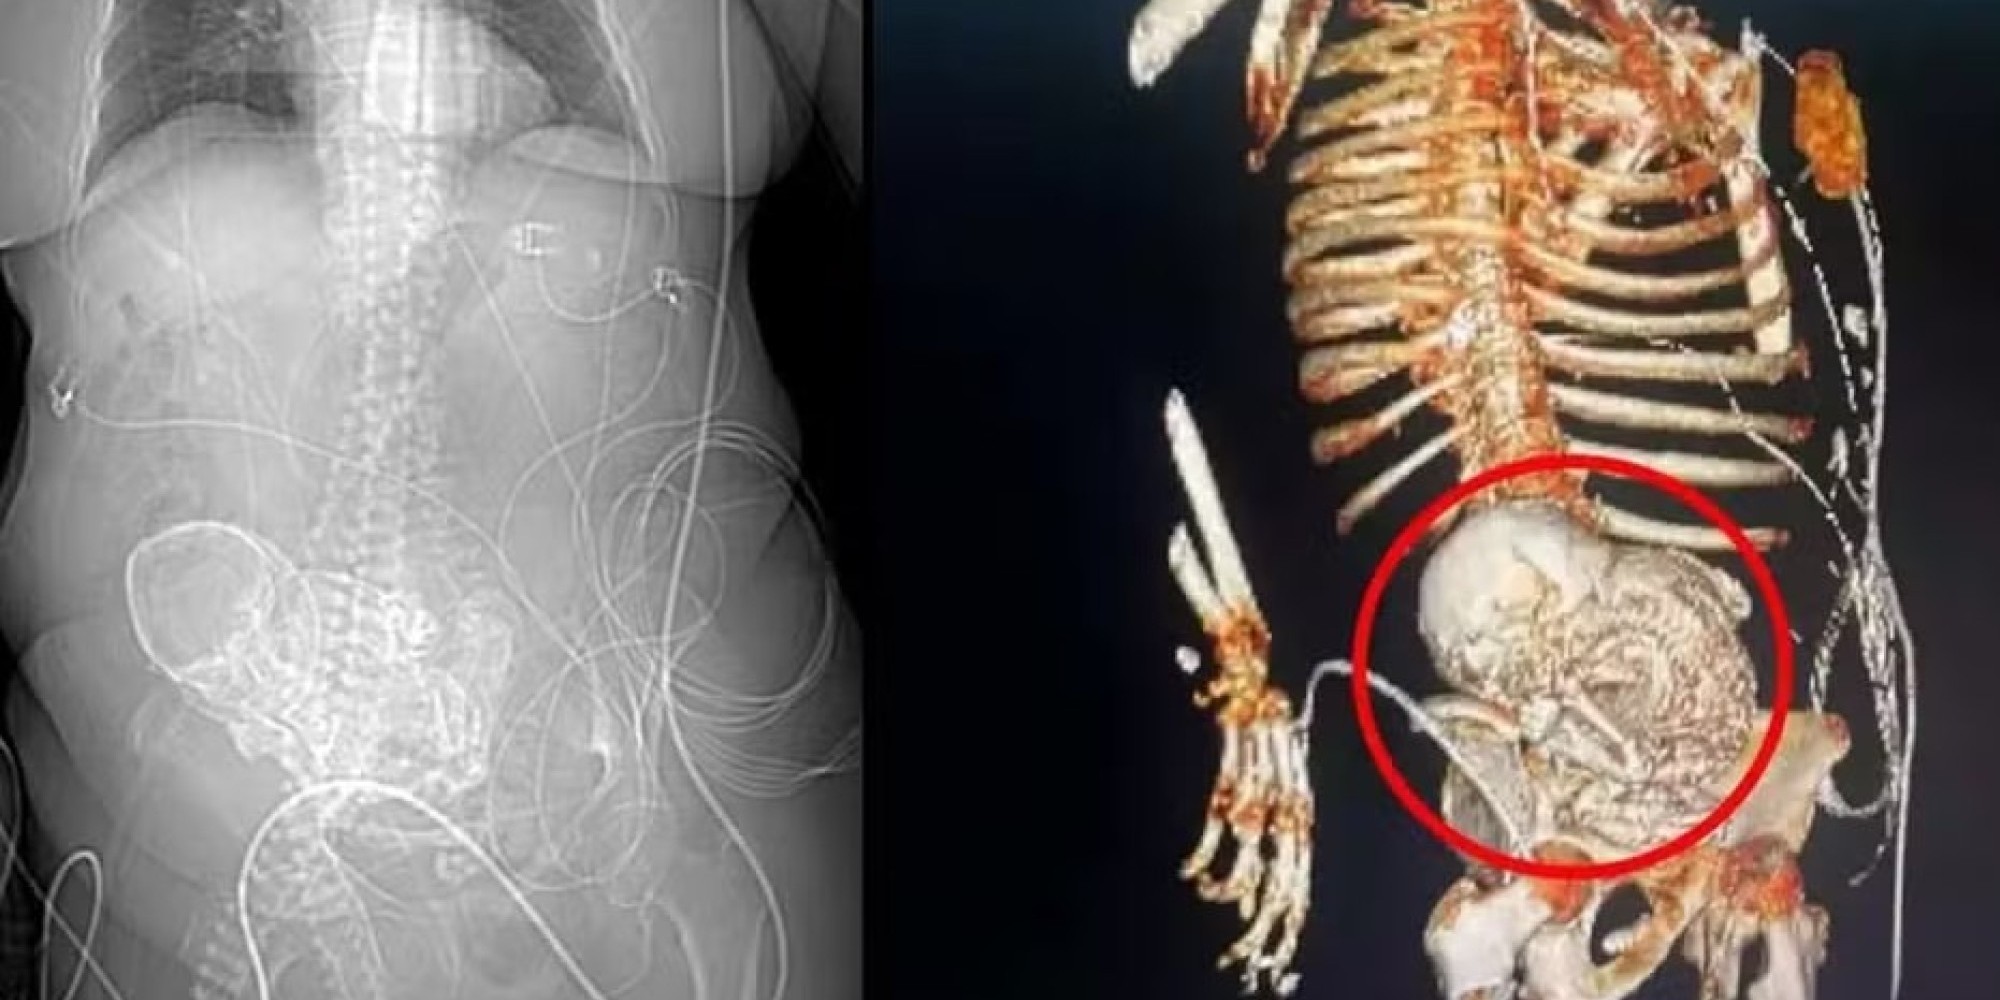

Uma idosa, de 81 anos, descobriu que carregava um feto calcificado ao ser encaminhada para o Hospital Regional de Ponta Porã, na região sul de Mato Grosso do Sul, com dores abdominais, de acordo com as informações do secretário de saúde da cidade, Patrick Derzi. A equipe médica suspeita que a mulher estivesse com o "bebê de pedra" no abdômen havia 56 anos, desde quando teve a última gestação. A condição é considerada raríssima por especialistas. A idosa, que era indígena e morava em um assentamento no município de Areal Moreira, morreu após a cirurgia para retirada do feto. A paciente deu entrada no Hospital Regional de Ponta Porã com um quadro de infecção grave em 14 de março. No mesmo dia, uma tomografia 3D constatou o feto calcificado na região do abdômen dela. Ao descobrir a existência do feto no corpo da idosa, a equipe de obstetrícia da instituição foi acionada e realizou a cirurgia para retirá-lo. Após o procedimento, a paciente foi encaminhada para uma Unidade de Tratamento Intensivo (UTI), mas morreu no dia seguinte. O motivo da morte foi um quadro grave de infecção generalizada, que ocorreu a partir de uma infecção urinária, segundo o secretário Patrick Dezir. De acordo com o secretário de saúde de Ponta Porã, a idosa morava em Aral Moreira, que fica a 84 quilômetros do município. Ela já tratava uma infecção urinária na cidade onde residia. Por causa da piora no quadro clínico, a idosa teve que ser transferida para o HR da cidade vizinha, onde a equipe médica chegou a suspeitar de um câncer. Após a idosa dar entrada no HR de Ponta Porã, em 14 de março, uma tomografia 3D foi solicitada para precisar o diagnóstico. O exame que identificou o feto calcificado no abdômen da mulher, de acordo com as informações da secretaria de Saúde de Ponta Porã.

FOTO – Divulgação